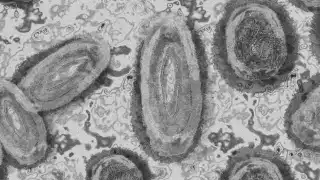

Luego que van ocho casos detectados viruela símica (conocida como del mono) en Quintana Roo y con la alerta de la Organización Mundial de Salud, autoridades estatales lanzan recomendaciones en la entidad a fin de frenar los casos.

Sin precisar la cepa de la viruela símica, la que se ha detectado en Quintana Roo es la clado IIb, que es diferente a la variante africana, que según los expertos es más agresiva y puede ser mortal identificada como clado I.

La Organización Mundial de la Salud (OMS) ha declarado la emergencia sanitaria mundial a causa de un brote de una nueva variante de este virus, la Ib, que es más letal y más fácil de transmitir. Todavía no se ha identificado ningún caso de este nuevo tipo en América Latina, según la dependencia federal, que puntualiza que la enfermedad “no tiene un tratamiento específico”.